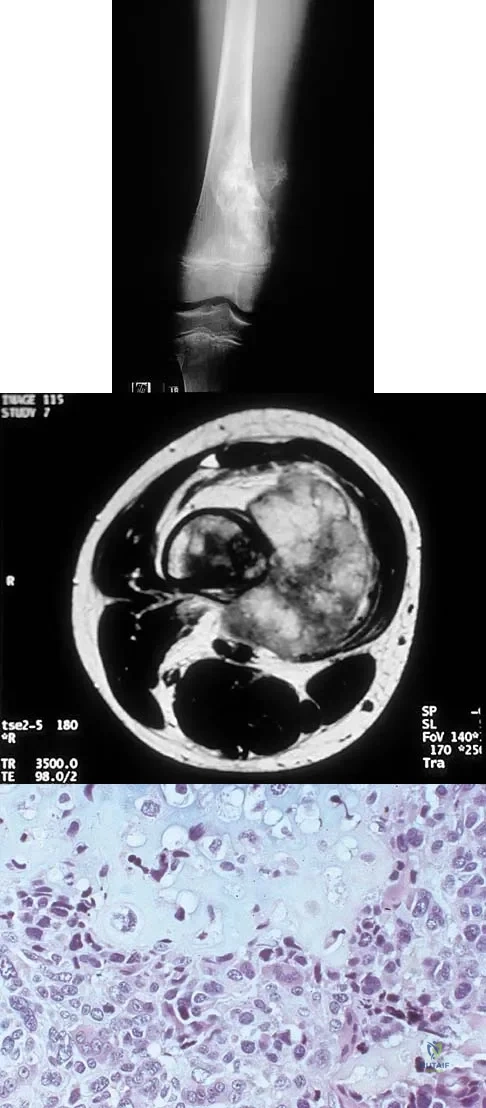

A 21-year-old man has had progressive right knee pain for the past 2 months that is exacerbated with weight-bearing activities. A plain radiograph and an MRI scan are shown in Figures 43a and 43b. A biopsy specimen is shown in Figure 43c. According to the Enneking staging system of tumor classification, the lesion should be classified as what stage?

Explanation